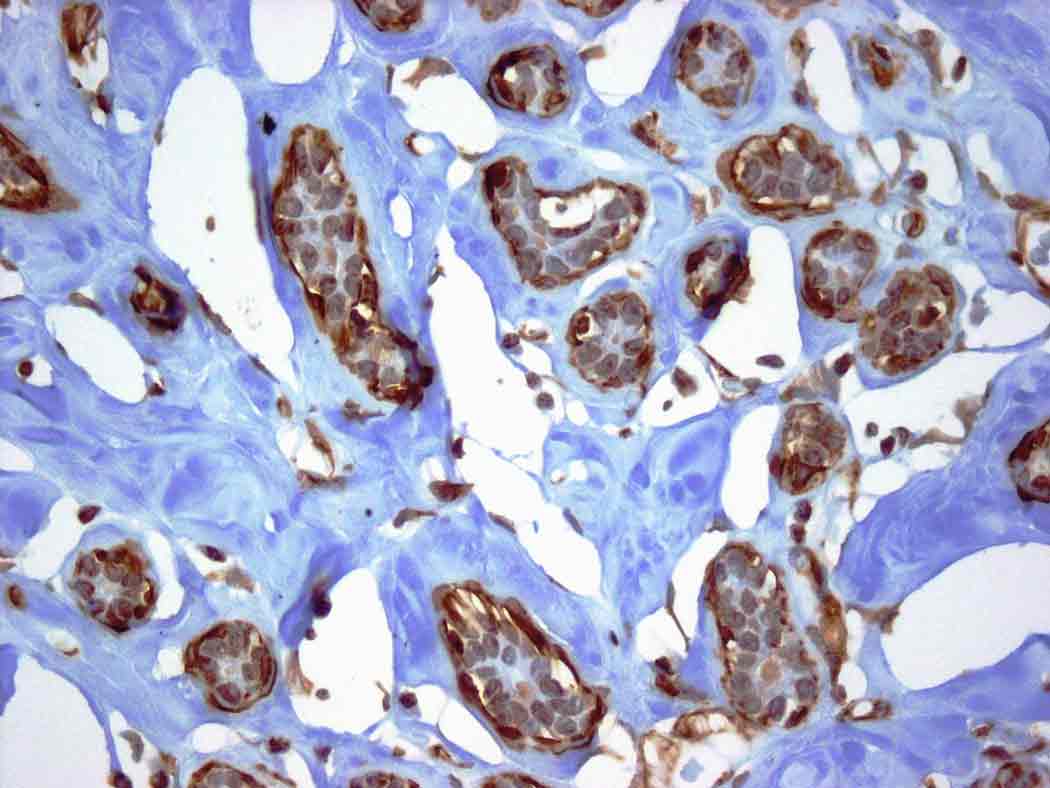

Nello studio in questione, scienziati nei Paesi Bassi e in Svezia rivelano che l’ACC è causato da un gene di fusione, che nasce dalla fusione di due geni sani. Essi sono giunti a questa conclusione dopo aver esaminato campioni tissutali di tumori ACC prelevati da diverse parti del corpo. Il fatto che tutti i campioni presentavano il gene di fusione – a prescindere dal fatto che derivassero da ghiandole salivari, seno o altro – indica che esso reppresenta un segno specifico della malattia – ha spiegato il team.

I due geni che compongono il gene di fusione sono il MYB e il NFIB. Il MYB svolge una serie di funzioni nell’organismo: oltre a controllare l’accrescimento cellulare, aiuta a provocare la morte di cellule che non sono più necessarie. Generalmente, l’attività del MYB è soppressa nelle cellule più mature. I ricercatori ipotizzano che con la fusione di MYB e NFIB, la cellula perde la sua capacità di controllare l’attività del MYB. Di conseguenza, esso si attiva, provocando una sovrapproduzione massiccia di una proteina anomala che possiede proprietà cancerogene.